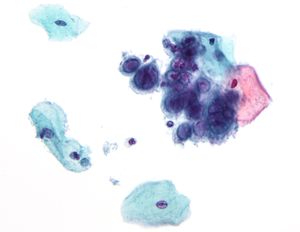

Micrograph showing the viral cytopathic effect of herpes (ground glass nuclear inclusions, multi-nucleation). Pap test. Pap stain.